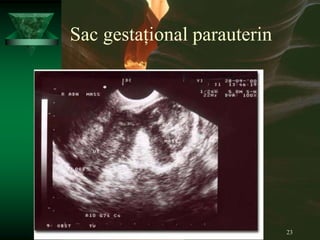

ECOGRAFIA

Un diagnostic pozitiv de sarcină extrauterină poate fi făcut dacă

se observă mișcări fetale în afara uterului.

De obicei această situație este foarte rară și cam târzie iar

așteptarea pentru a o găsi întârzie punerea diagnosticului și

crește riscul de ruptură tubară.

În practică, ecografia este folosită pentru a identifica o sarcină

intrauterină.

Criteriul ecografic tradițional pentru diagnosticul de sarcină

ectopică este lipsa unui sac gestațional în uter și pacienta

are mai mult de 6 săptămâni de amenoree.

Problema cu acest criteriu este că o treime dintre pacientele cu

sarcină extrauterină nu mai știu data când au avut ultimul

ciclu

Sac gestațional parauterin